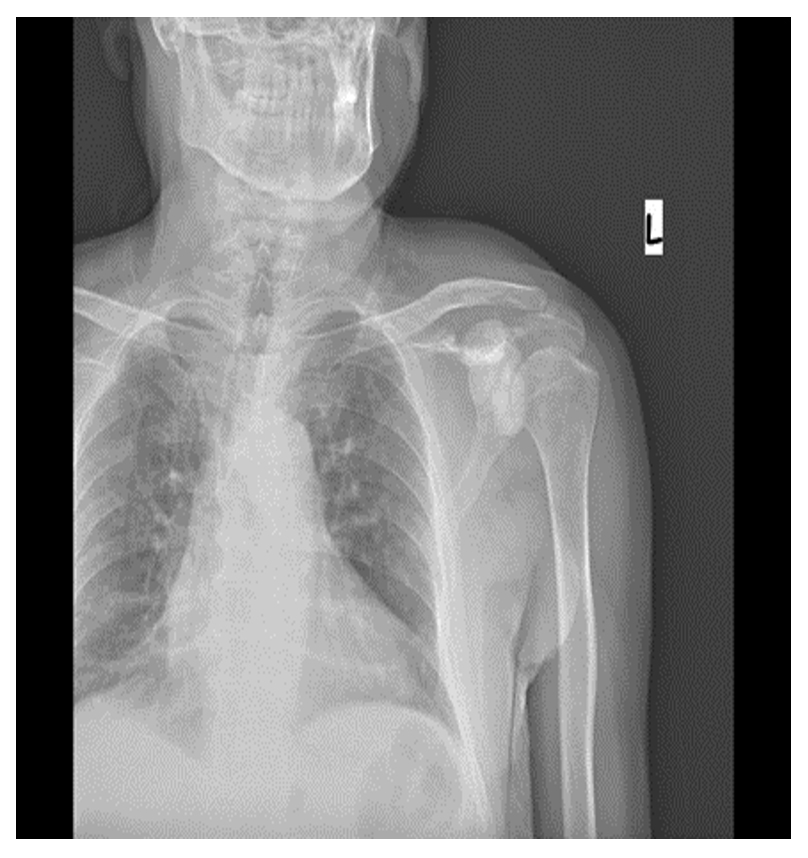

Ameliyat Öncesi: Röntgende sol skapulada düzensizlik ve skleroz görülmekte.